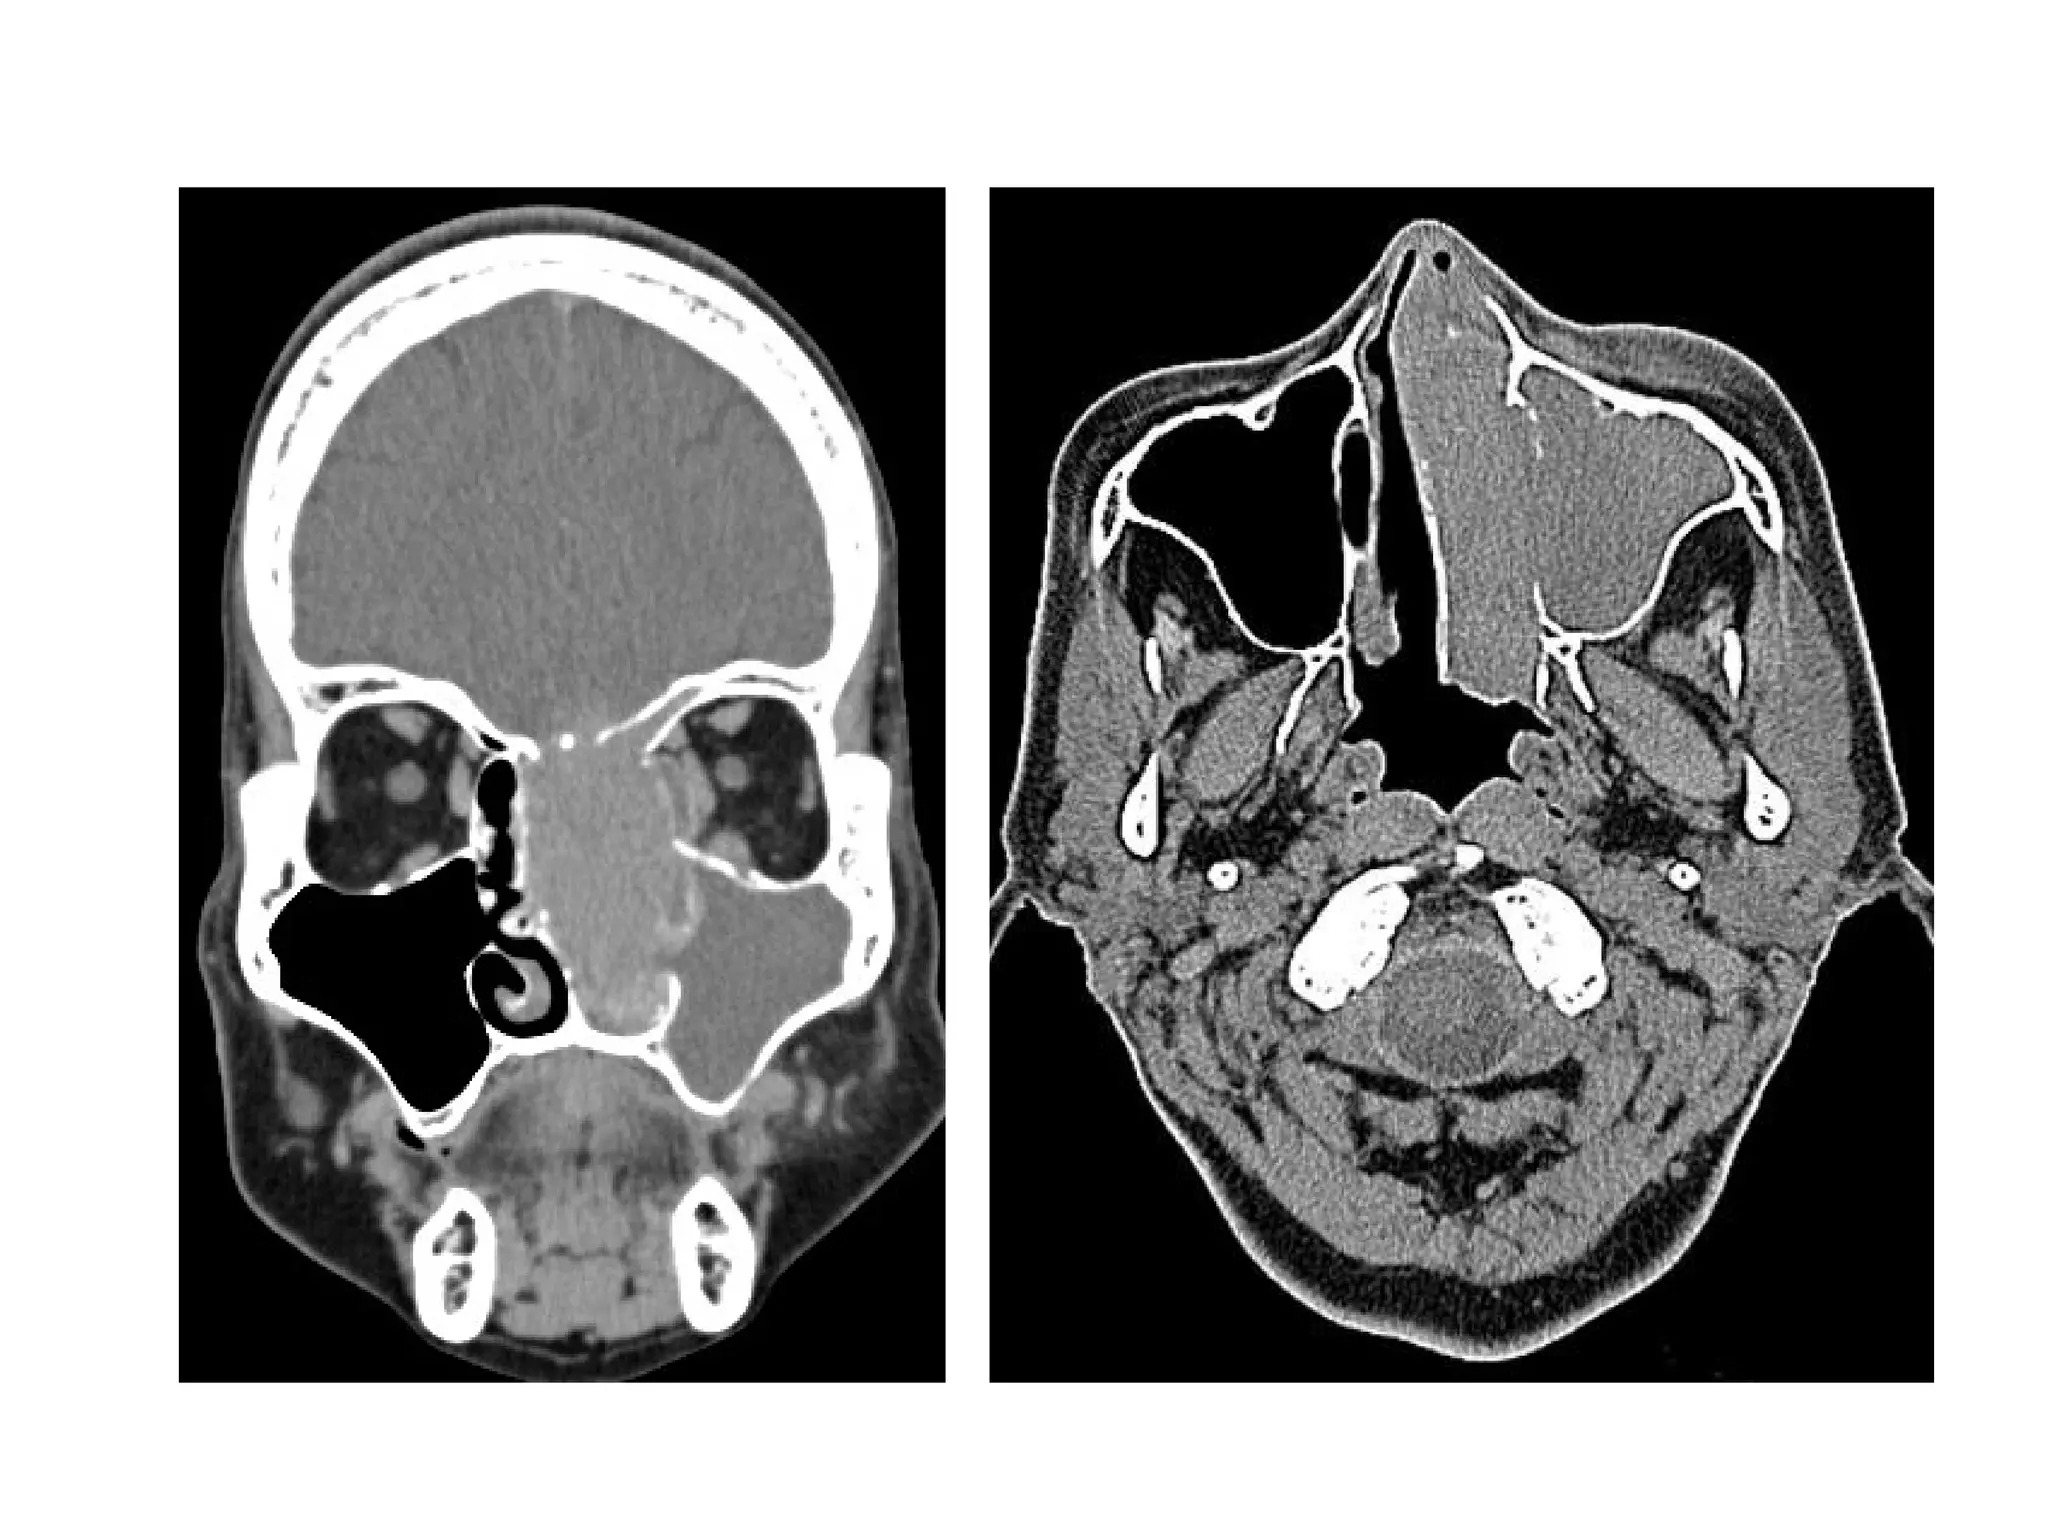

f) Mucocele :

1-Incidence :

-True cystic lesion lined by sinus mucosa

-Mucoceles occur as a result of complete

obstruction of sinus ostium (inflammation ,

trauma & tumor)

-The bony walls of the sinus are remodeled

as the pressure of secretions increases

2-Location :

-frontal 65% > ethmoidal 25% > maxillary

>10%

-Sphenoidal (rare)

3-Radiographic Features :

-Rounded soft tissue density

-Typically isodense on CT

-MR signal intensity :

Low T1 , high T2 : serous content

High T1 , high T2 : high protein content

Dark T1 and T2 : viscous content

-Distortion and expansion of bony sinus walls

-Nonenhancement unless infected (mucopyocele) ,

rim enhancement

-Complication : breakthrough into orbit or anterior

cranial fossa